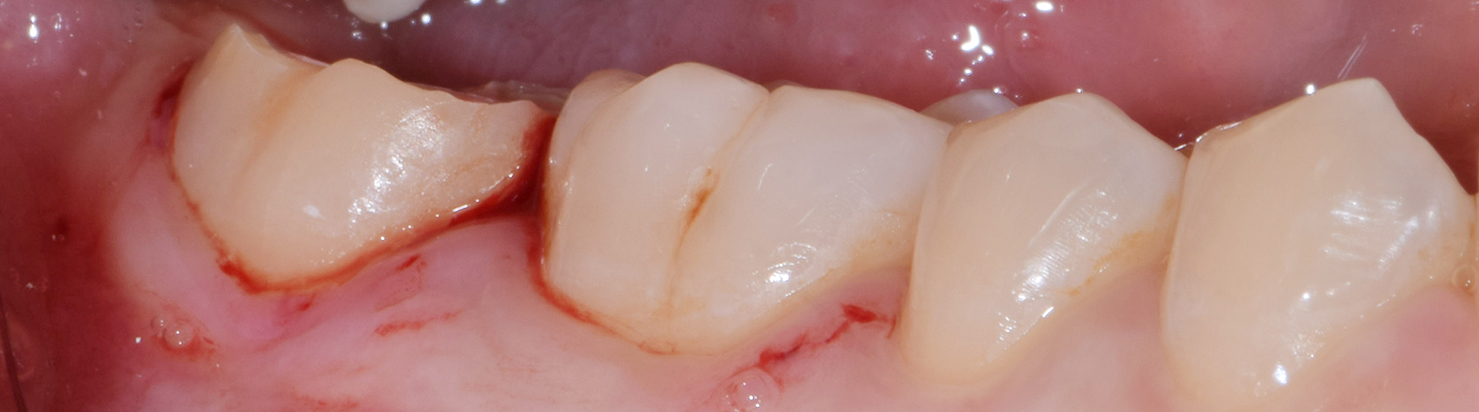

Crown lengthening (Posterior teeth)